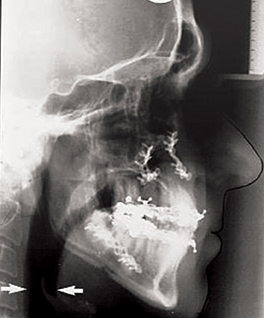

Figure 2: Demonstration of changes to posterior airway space by maxillary

advancement osteotomies. Preoperative (top) postoperative (bottom).

It has become increasingly recognised that carrying out mandibular and maxillary osteotomies can also have a profound positive or negative effect on the posterior airway space at both the level of the tongue base and the palate, which is predictable and dependent on the direction of movement. By advancing the mandible and the maxilla 8-10mm especially in combination with an advancement genioplasty the posterior airway space can be greatly improved. This has been measured on lateral cephalometric radiographs and more recently 3D computerised tomography (CT) has demonstrated the increased airway volume achieved [6]. More importantly than radiographic appearance, however, is the resolution in symptoms of OSA and demonstrable improvement in polysomnography studies. It is becoming increasingly recognised that orthognathic mandibular setback surgery can lead to conversion into OSA [7].